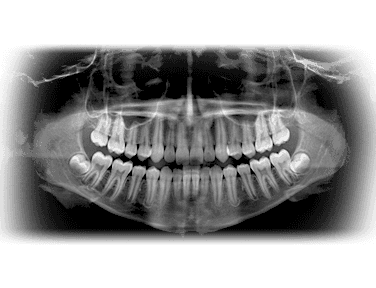

For the first time in the 100-year history of dental X-rays (radiography), an extraordinary new technology surpasses the diagnostic abilities of traditional film. It does so with substantially less radiation exposure to you.. and us. This system has truly amazing diagnostic tools, making the image quality simply unmatched.

Lockheed Martin, the aerospace manufacturer of the Magellan Venus Spacecraft and the Hubble Telescope designed the digital X-ray sensor that is the heart of this technology. The sensor is very special as it has a uniquely shaped design for your optimum comfort. No more sharp edges like the old film had. This allows for increased positioning accuracy.

This system allows for the ability to instantly produce the very best possible diagnosis and produces up to 90% less radiation.